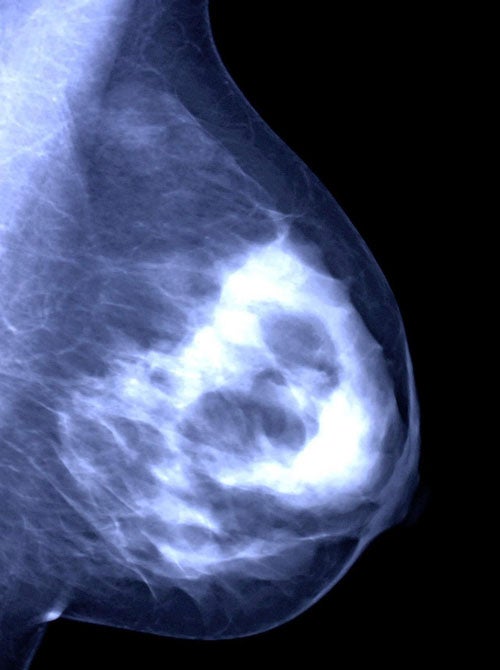

Two trials involving almost 4,500 women with breast cancer found that reducing the overall dose of radiation by 20 per cent and the number of sessions by 40 per cent cut side effects without increasing cancer recurrence. The finding could mean a reduction in the international-standard radiotherapy schedule for early breast cancer, which says that women should receive 50 gray of radiation in 25 equal doses over five weeks. It could also have implications for other cancers of glandular tissue, such as prostate cancer.

In women with breast cancer, radiotherapy is normally given after chemotherapy. The present regime means women must attend hospital five days a week for five weeks, spending an hour or more queuing for the radiotherapy machine, being correctly positioned under it and receiving their daily dose. Women in the two trials, called Start A and B (Standardisation of Breast Radiotherapy Trial), attended clinics three days a week over five weeks with a total dose of between 39 and 41.6 gray, compared with the normal 50 gray.

Five years on, recurrence rates of breast cancer in women on both trials were no different from those who had the standard treatment, but long-term side effects on the breast of hardening (due to fibrosis) and shrinkage were reduced. The research was done in 17 UK centres in the first trial and 23 centres in the second trial. The findings are published online in Lancet Oncology and The Lancet.